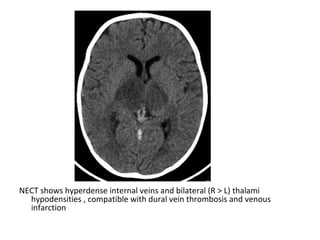

NECT shows hyperdense internal veins and bilateral (R > L) thalami

hypodensities , compatible with dural vein thrombosis and venous

infarction